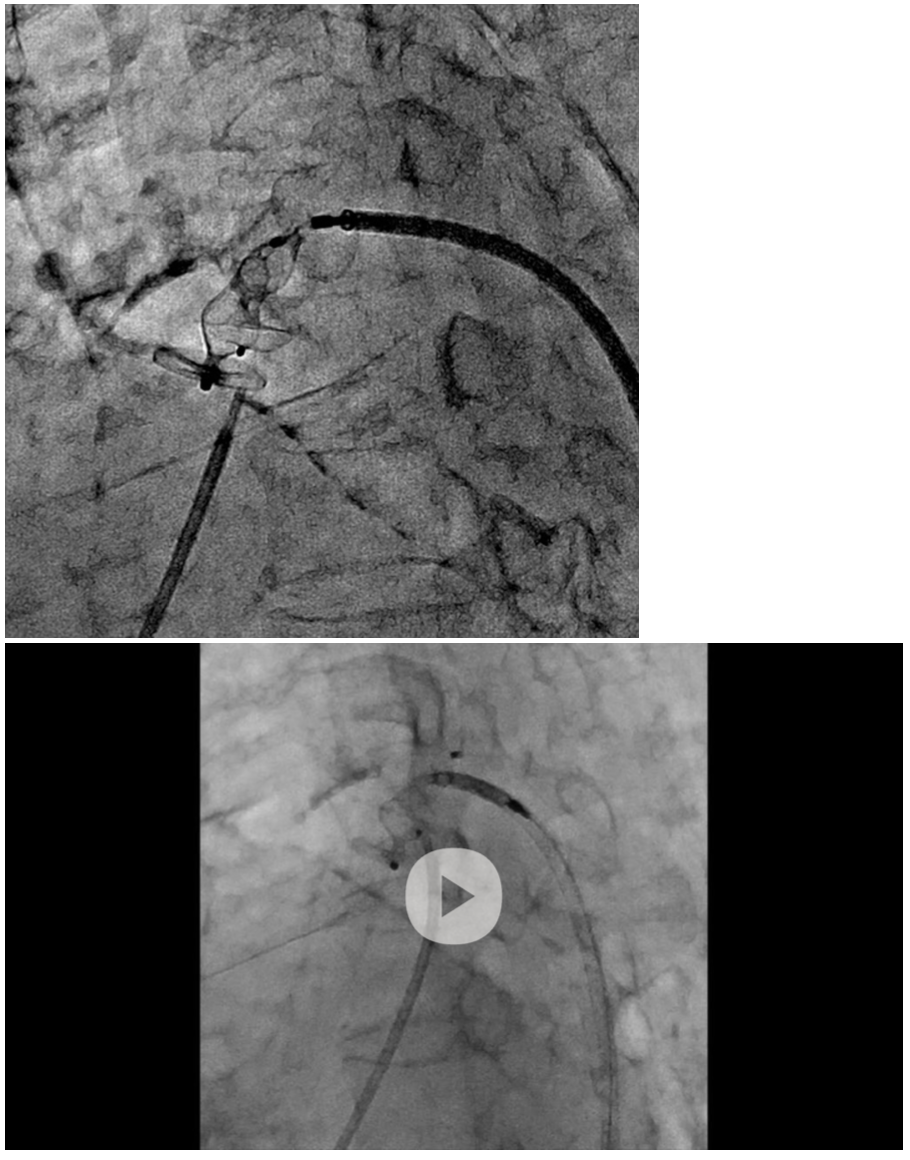

We selected a 6/6 Amplatzer Duct Occluder II (ADO II) (Abbott) device, and final angiography showed a slight residual shunt through the PDA. The ADO II device was released with the hope that the residual shunt would disappear due to endothelialization in the chronic phase. However, transthoracic echocardiography showed no improvement in the residual shunt a few months after the procedure. Her symptoms gradually worsened.

We chose re-intervention for the residual shunt. Intravascular ultrasound revealed that an incomplete closed space outside the ADO II caused the residual shunt (Figure 3, Video 2). We concluded that the ADO II device was over-stretched and not well-positioned due to severe calcification of the PDA. An Amplatzer Vascular Plug II (AVP II) (Abbott) 14/10 was deployed in the space (Figure 4, Video 3), and the PDA flow disappeared completely.